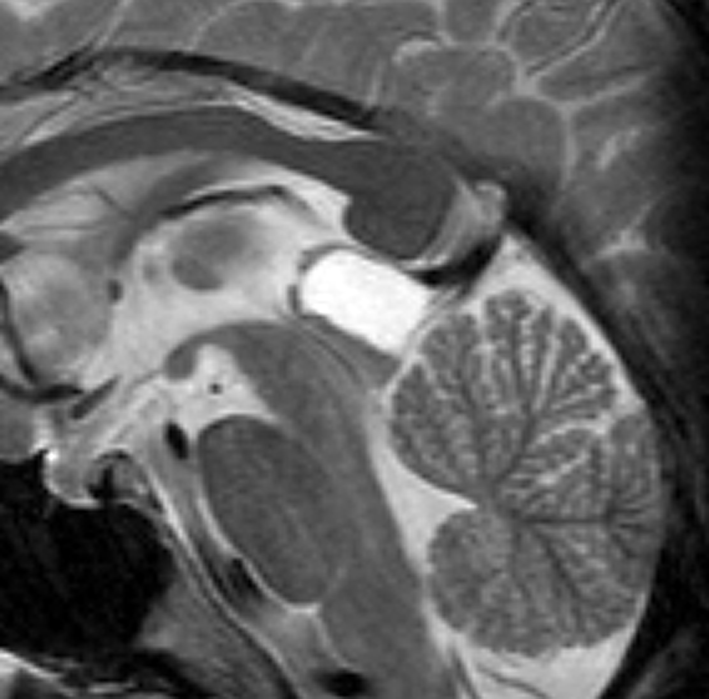

とても珍しい高齢者の松果体のう胞

79歳女性に偶然発見されたものです。10年くらい大きくなっていません。高齢者での大きな松果体のう胞はまれです。